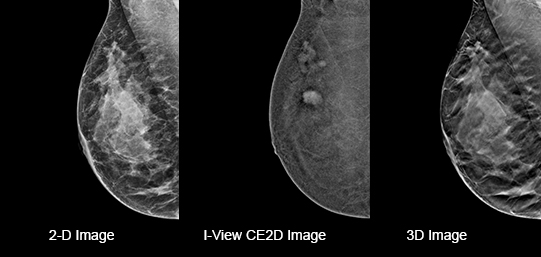

Hologic Selenia® Dimensions, tek bir tarama işleminde hem 2D dijital mamografi hem de gelişmiş 3D tomosentez teknolojisini bir arada sunar. Bu yenilikçi yaklaşım, radyologların meme dokusunun detaylarını daha eksiksiz değerlendirmesine olanak tanır ve teşhis doğruluğunu artırır. C-View™ sentezlenmiş 2D görüntü teknolojisi sayesinde, radyasyon dozu analog mamografi seviyelerine çekilirken, görüntü kalitesinden ödün verilmez. Bu özellik, özellikle yoğun meme dokusuna sahip hastalarda yüksek tanı güvenilirliği sağlar ve erken kanser tespitinde kritik rol oynar.

Hologic Selenia® Dimensions, C-View™ sentetik 2D görüntüleme teknolojisi sayesinde, 3D tomosentez verilerinden oluşturulan yüksek kaliteli 2D mamografi görüntüleri sağlar. Bu yöntem, geleneksel çiftli tarama yerine tek bir 3D tarama ile hem 3D hem de 2D görüntü elde edilmesini mümkün kılarak radyasyon dozunu önemli ölçüde azaltır. Klinik çalışmalarda, C-View™ teknolojisiyle radyasyon dozu %40-50 oranında düşürülürken, görüntü kalitesi ve tanı güvenilirliği korunmuştur. Böylece hastalar daha az radyasyon riskiyle erken ve doğru teşhis imkanına kavuşur.

iView - Kontrast Destekli Mamografi ile Daha Fazla Gör

iView Contrast Enhanced , Hologic’in 3D mamografi platformlarına entegre edilebilen, kontrast madde destekli bir görüntüleme yazılımıdır. Bu teknoloji, damarlanma artışı gösteren lezyonları klasik görüntüleme tekniklerine göre çok daha belirgin hale getirerek malignite şüphesi taşıyan dokuların daha net değerlendirilmesini sağlar. Dinamik kontrast yapısıyla, anjiyografi benzeri bir görüntüleme elde edilir; bu sayede hem morfolojik hem de fonksiyonel bilgi birlikte sunulur.

Özellikle yoğun meme yapısına sahip ya da klasik mamografi ve ultrason ile net sonuç alınamayan olgularda, iView CE, manyetik rezonans (MR) alternatifi olarak tercih edilebilir. Hologic’in özel yazılım algoritmaları sayesinde düşük dozda kontrast ile yüksek duyarlılıkta tarama yapılabilir.

Intelligent 2D™, Hologic’in 3D tomosentez verilerini kullanarak yüksek kaliteli sentetik 2D görüntüler oluşturan gelişmiş bir görüntüleme teknolojisidir. Bu teknoloji sayesinde, ayrı bir 2D çekim yapmaya gerek kalmadan tanısal değeri yüksek 2D görüntüler elde edilir. Böylece hem radyasyon dozu azaltılır hem de hastaya ikinci bir çekim uygulanmasına gerek kalmaz.

Gelişmiş algoritmalar, her taramada ayrıntılı veri analizi yaparak klasik 2D görüntülere eşdeğer ya da daha üstün nitelikte sonuçlar sunar. Ayrıca, bu teknoloji sayesinde veri boyutları küçülür, görüntüler daha hızlı işlenir ve radyologların değerlendirme süresi kısalır.